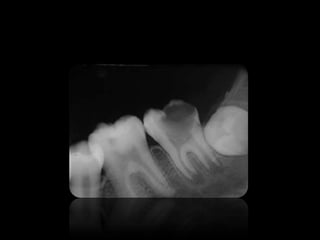

ABSCESO PERIAPICAL